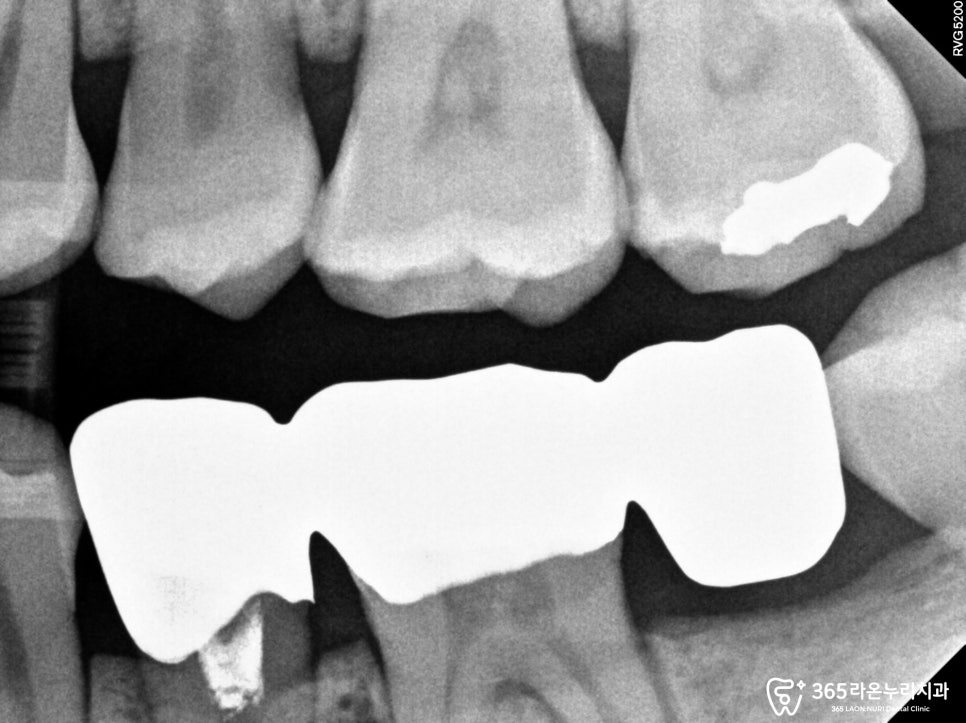

그리고 남촌동 치과 에서

엑스레이를 통해 30번대

어금니를 보면 우식증으로 인해

치조골이 내려 앉은 모습과

그로인해 음식물이 저류하면서

문제가 생긴 모습을 확인할 수 있었습니다.